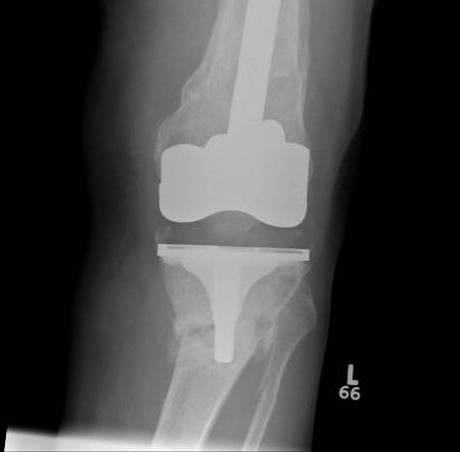

1.  Lateral locking plate

TKR Periprosthetic Fracture Minimall Dislplaced CTTKR Periprosthetic Fracture Locking Plate APTKR Periprosthetic Fracture Locking Plate Lateral

Technique

Minimally invasive technique

- may need unicortical screws distally

Results

Kolb et al J Trauma 2010

- 19 patients treated with LISS plate

- 2 delayed union

- otherwise good union rate with minimal complications and good ROM

Streubel JBJS Br 2010

- compared proximal fractures to distal (beyond the femoral prosthesis)

- showed similar healing rates in each group treated with locking plates